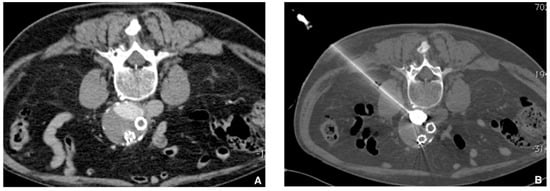

Figure 9. Type 2 endoleak from lumbar ateries. (A) Computer tomography (CT) scan with contrast injection in procubitus position showing posterior opacification of the periprothetic aneusrysmal sac (nidus). (B) Translumbar puncture of the nidus of the endoleak under CT guidance with a metallic needle. Insertion of a microcatheter inside and embolization of the nidus with a Glubran®2/lipiodol mixture (1:4 ratio) until complete nidus opacification.

Jcm 10 04320 g009